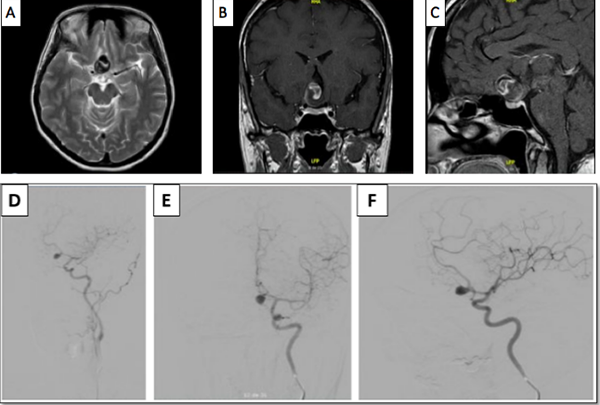

Luego del análisis del caso, y teniendo en cuenta la presencia del trombo intracavitario, el cuello del aneurisma, la posición favorable del saco aneurismático, y la edad de la paciente, se decidió que la cirugía era la mejor opción terapéutica, se realizó una craneotomía pterional derecha, y un abordaje transilviano bajo visión microscópica. Se encontró un aneurisma de gran tamaño dependiente de la AcomA (Figura 2), con dirección anteroinferior, calcificación en las paredes del domo y signos de trombosis. Una vez se identificó el cuello, y ambas A1 y A2, se posicionó un clip recto de 9 mm, que luego se reacomodó con otro clip definitivo de 9 mm, se retiró el previamente colocado, quedando con un solo clip definitivo. A continuación se comprobó la permeabilidad de los vasos A1 y A2, así como de la arteria recurrente de Heubner ipsilateral con doppler intraoperatorio. Se procedió con la disección del domo del aneurisma y trombectomía con aspirador ultrasónico, dejando el interior del aneurisma friable, y descomprimiendo de esta manera el nervio y el quiasma óptico. El procedimiento finalizó sin complicaciones, la paciente mejoró del déficit en el postoperatorio inmediato, y se llevó a arteriografía de control al día siguiente de la intervención, con la que se confirmó el adecuado clipaje de la lesión (Figura 3).

Figura 2

Secuencia quirúrgica. Se exponen los pasos más importantes. Disección de estructuras alrededor del aneurisma, el punto blanco señala el cuello del aneurisma expuesto y en azúl el domo (A). Clipaje del cuello (B). Aneurismectomía y trombectomía. La marca de color azúl indica el lóbulo temporal izquierdo, en blanco se observa el lóbulo frontal, y debajo de este se encuentra el aneurisma de ACoA abierto, por encima del domo marcado en color negro se puede observar el nervio óptico, y adyacente a este, en color rojo, se observa la arteria carótida interna, detrás del domo del aneurisma y en color amarillo, la arteria cerebral anterior izquierda cursa paralela al cuello del aneurisma (C)